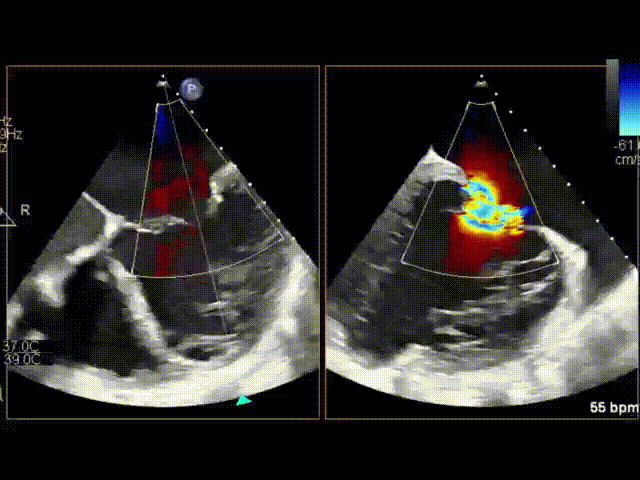

下午第二台手术直播由复旦大学附属中山医院魏来教授主刀。这是一名60岁老年男性,主诉:反复胸闷、气促1年余,体检:心尖部III/6级收缩期吹风样杂音。心功能IV级。既往高血压8年,三尖瓣生物瓣置换术后13年,永久起搏器植入术后7年。患者经多年规范GDMT治疗,但症状仍进行性加重,无法耐受。

患者心电图提示室性早搏二联律,心超提示左房巨大、二尖瓣环极度扩张,前后叶分离无对合高度。同时左心室扩大、后叶栓系,导致极重度二尖瓣反流,EF:48%,经综合考虑为房性+室性功能性二尖瓣反流,预计外科二尖瓣成形手术效果不佳,复发率高。患者为再次心脏手术,且STS评分7.599%,属于常规外科手术高风险,故首选介入治疗。

经CT评估,患者二尖瓣环过大,不适合经导管二尖瓣置换术TMVR,可考虑经导管二尖瓣缘对缘技术TEER,但也面临瓣叶对合高度不足、反流束宽度过大等解剖挑战。

术前二尖瓣极重度反流

术中通过食道超声再次确认患者二尖瓣反流主要在2区,同时也累及1区和3区,反流极重度(+++++),反流口面积达到8*19mm,单夹无法有效解决反流问题。魏来教授临时改变手术方案,决定先在相对困难的3区尝试夹合,然后在2区平行释放第二个夹子。术中魏教授在心脏超声室潘翠珍教授、李伟教授鼎力配合下,通过娴熟的技术,完美达成了术前的既定方案,术后食道超声提示二尖瓣仅轻度反流(+),平均压差仅3mmHg。魏教授和李伟教授均连声感慨:“出乎意料,手术效果超过预期。”

3区释放第一个夹合器后该区反流消失

2区释放第二个夹合器后反流从极重度减少到轻度